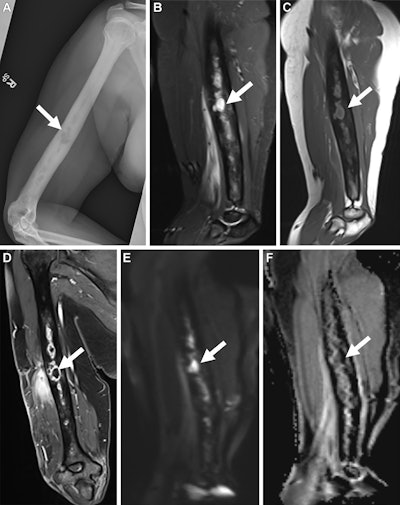

Musculoskeletal Infection Reporting and Data System (MSKI-RADS) category V findings in a 35-year-old female patient with infection in the right humerus. (A) Frontal radiograph, sagittal (B) short tau inversion recovery and (C) T1-weighted images, and (D) coronal Dixon fast spin-echo three-dimensional T1-weighted postcontrast image of the right humerus show osteomyelitis with intraosseous abscess (arrow), consistent with MSKI-RADS category Va, defined as highly suggestive of osteomyelitis. Corresponding (E) diffusion-weighted image and (F) apparent diffusion coefficient map show high signal intensity on E and low signal intensity on F, consistent with abscess (arrow). Image and caption courtesy of the RSNA.